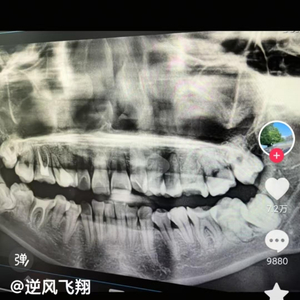

记者联系到该女子的哥哥和丈夫。其哥哥表示,3月12日妹妹去该医院拔智齿时,医生拔了两颗智齿和一颗好的牙齿,有两颗智齿没有拔掉。该医生发现拔错牙齿后,又将已经拔掉的好牙错塞到了智齿的位置,同时用铁丝将牙齿草草固定。

哥哥说:“他还隐瞒了我妹妹,擅自把我妹妹的病历修改了,我妹妹当时不知道,后来去别的医院拍片后才知道那个医生搞得有多离谱。”

因当时打麻醉是打在智齿部位,原生好牙的位置并未麻醉,医生是“硬生生给它拔下来的”。